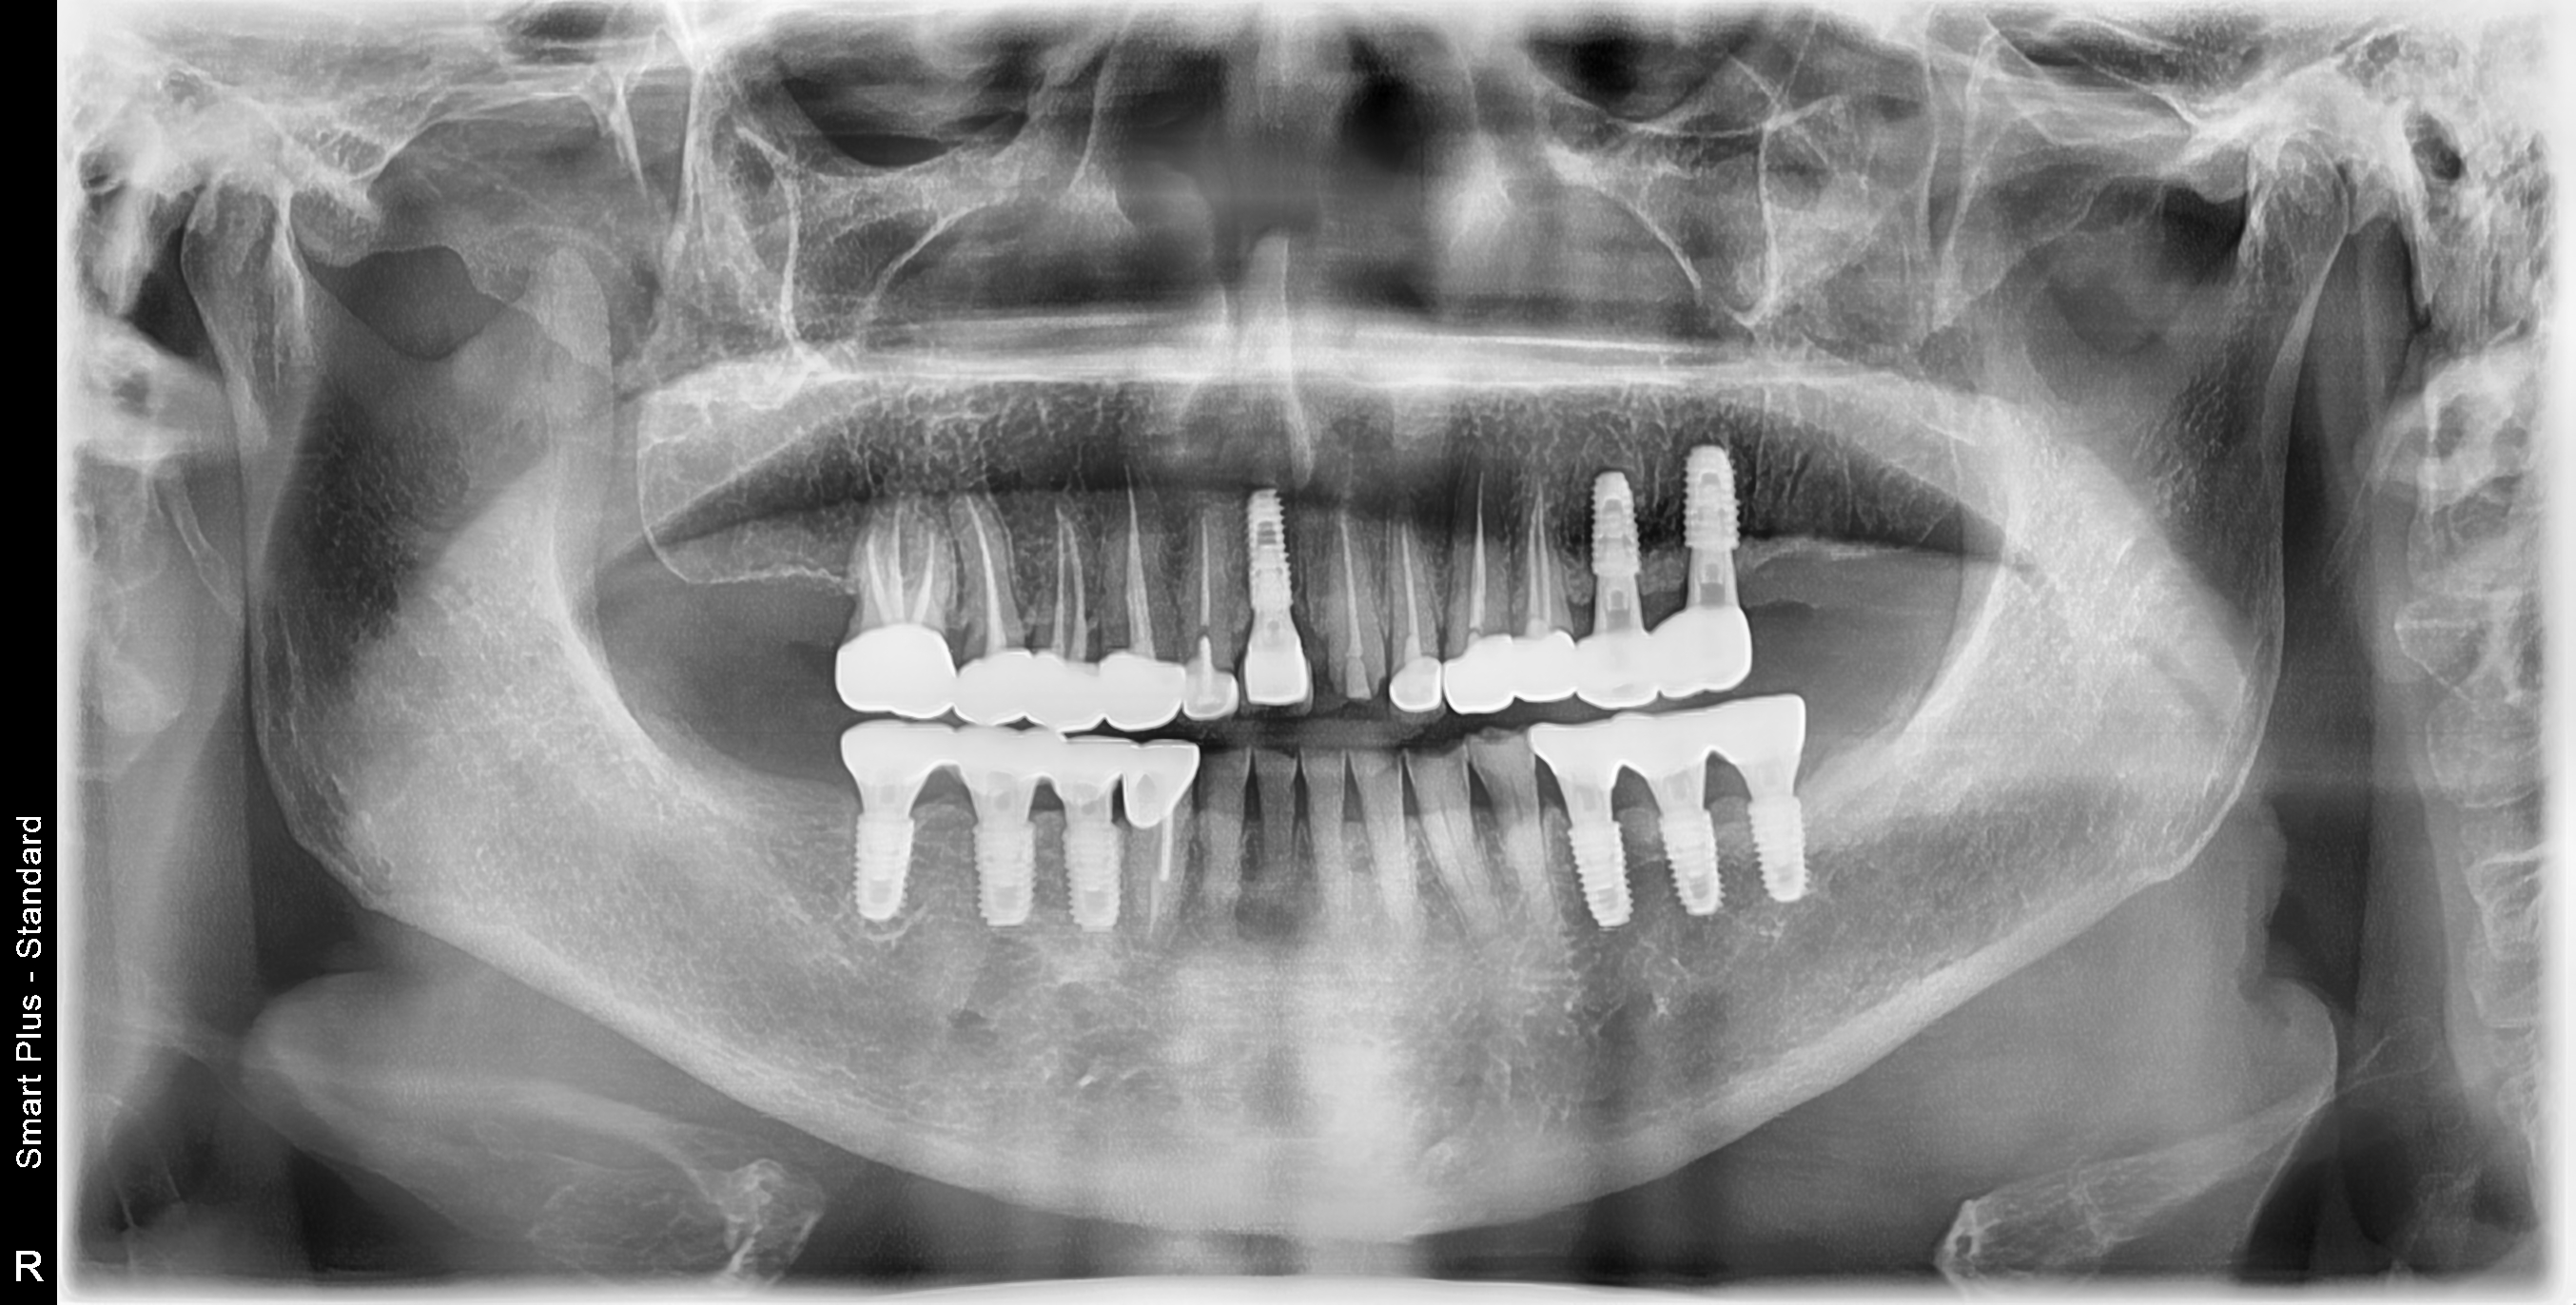

[임플란트] 제목 : 치아상실 후 임플란트

다수 치아의 상실 후 임플란트 치료